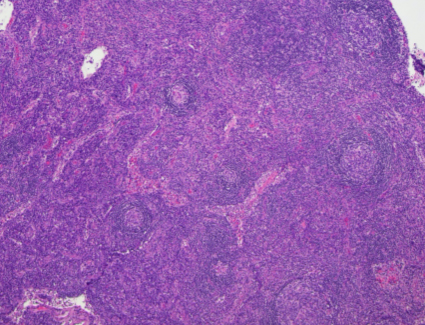

H&E (40x magnification)

The low power view shows lymph node tissue with abnormal follicles, including partial hyalinization, regression of germinal centers, and concentric mantle zone lymphocytes showing "onion skinning" appearance. Several follicles show prominent penetrating venules. No Hodgkin-Reed-Sternberg cells or LP cells were identified.